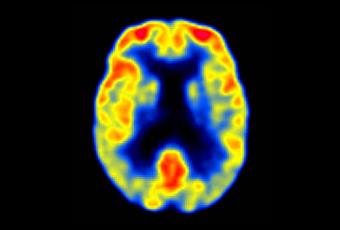

PET en Alzheimer leve © Keith A. Johnson y J. Alex Becker

A todos los sujetos participantes se les practicaron pruebas de imagen mediante PET–[18F]FDDNP, midiendo los valores de captación en las áreas de interés temporales media y lateral, del cingulado posterior, parietal, frontal y global, además de aplicarles una batería neuropsicológica para medir cinco dominios cognitivos: memoria, lenguaje, atención (y velocidad de procesamiento de la información), función ejecutiva y capacidad visoespacial. Todo ello realizado tanto basalmente (al inicio del estudio) como a los dos años de seguimiento. La captación incrementada en las regiones frontal, del cingulado posterior y global se correlacionaron con progresión del declive de la memoria a los dos años de seguimiento para todo el grupo de participantes, tanto los que ya sufrían deterioro cogntivo leve al inicio del estudio como aquellos que basalmente mostraron un envejecimiento normal. Además, se comprobó que una mayor captación basal estaba asociada a un futuro declive en la mayoría de los dominios cognitivos, incluyendo el lenguaje, atención, función ejecutiva y capacidades visoespaciales. En el grupo con deterioro cogntivo leve, la captación frontal y parietal arrojó la mayor precisión diagnóstica en la identificación de convertidores a enfermedad de Alzheimer versus no convertidores a los dos años, bastante por encima de la hipercaptación en la región temporal media. En sus conclusiones, los autores afirman que, en base a sus resultados,«Los patrones de captación regional en el PET–[18F]FDDNP son consistentes con los patrones neuropatológicos conocidos de acumulación de placas y ovillos, difundiéndose desde la región temporal media a otras regiones neocorticales a medida que progresa la enfermedad. Como los patrones de captación predicen el declive cognitivo futuro y van aumentando a lo largo del tiempo a la par que el declive cognitivo, el escaneado con PET–[18F]FDDNP puede tener utilidad práctica para identificar a personas con riesgo de futuro declive cognitivo, así como para el seguimiento de la efectividad de las intervenciones novedosas que se diseñen para prevenir o retrasar la neurodegeneración y el declive cogntivo».Referencia bibliográfica: Gary W. Small, Prabha Siddarth, Vladimir Kepe, Linda M. Ercoli, Alison C. Burggren, Susan Y. Bookheimer et al. Prediction of Cognitive Decline by Positron Emission Tomography of Brain Amyloid and Tau. Arch Neurol. 2012;69(2):215-222.